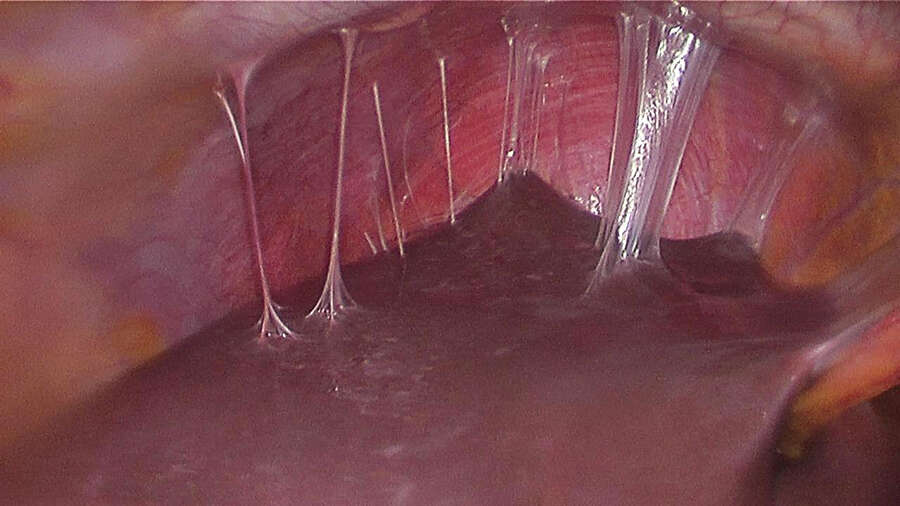

Fıtık onarımının dünya çapında en yaygın cerrahi prosedürlerin başında geldiğine işaret eden Prof. Dr. Esra Karaca, her yıl yaklaşık yirmi milyon hastanın fıtık gelişimine bağlı olarak ameliyat edildiğini açıkladı. Karın duvarında oluşan defektin, mesh adı verilen bir tıbbi tekstil materyali implante edilerek onarılmasının da bu alanda yapılan en yaygın cerrahi müdahalelerden birisi olduğunu söyleyen Prof. Dr. Esra Karaca; “Bununla beraber, kullanılan meshler ciddi adezyonlara neden olmaktadır. Daha önce fıtık ameliyatı olmuş hastaların %90'ından fazlasının ameliyat sonrası adezyon semptomları gösterdiği tespit edilmiştir. Adezyonlar ise, kronik karın ağrılarına ve iç organlarda ölümcül tıkanıklıklara yol açabilmektedir. Yeni ürünler denenmesine rağmen, post-operatif adezyon henüz başarıyla önlenememiştir. BUÜ Tıp Fakültesi Hastanesi’nden Türkiye ile ilgili bir projeksiyon yapılarak, ülkemizde bir yılda kullanılan fıtık mesh sayısının 100 bin civarında olduğu sonucuna varılmıştır. Bu nedenle; proje kapsamında geliştirilecek başarılı bir kompozit meshin, yurt dışından mesh ithalatını önemli oranda azaltacağı öngörülmektedir” açıklamasında bulundu.

Karaca ayrıca projede, karın fıtıklarının onarımında kullanılmak üzere çörek otu yağı içeren anti-adezyon özellikli nanolifli yüzey ile takviyelendirilmiş PP örme mesh yapıların geliştirilmesi ve kompozit meshlerin fıtık onarımı ve adezyon önleme performansının in vitro ve in vivo çalışmalarıyla değerlendirilmesini amaçladıklarını da sözlerine ekledi.